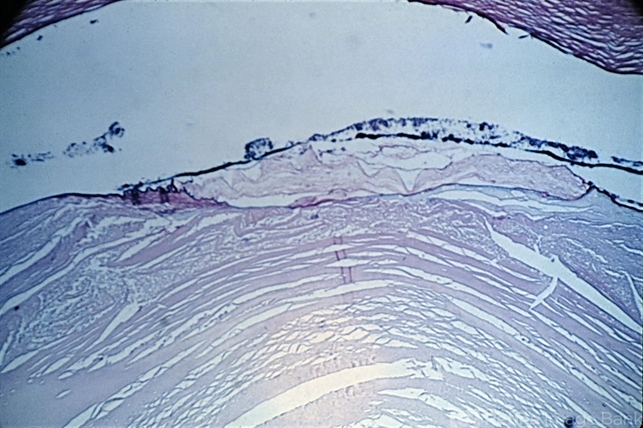

- anterior subcapsular polar cataract

- Anterior subcapsular cataract. Plaque of tissue beneath the anterior capsule replacing epithelium (PAS x21).